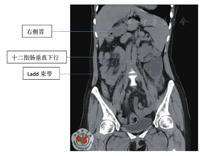

患者女,40岁,身高160 cm,体质量52 kg,因2 d前无明显诱因出现左下腹部持续性绞痛,于2018年10月19日急诊入院,体温37.7℃,脉搏112次/分,伴稍恶心,无呕吐、放射痛、发热,无腹泻、血便,无尿频、尿痛等症状。1 d前曾在当地社区医院以"急性肠炎"给予抗感染、解痉等治疗,自觉症状有所缓解,次日午间症状再次加重。查体:左下腹压痛(+)、反跳痛(+),局部腹肌紧张明显。行腹部CT平扫检查示:结肠走行反位,右半结肠位于左上腹,阑尾增粗伴周围渗出,周围间隙模糊,阑尾最粗约1.7 cm,临近盲肠壁稍增厚;胃腔大部分位于右侧,十二指肠垂直下行,可见Ladd束带;肝脏体积明显增大;脾脏受推挤,位于左侧肾上腺前方(图1,图2,图3)。诊断为"结肠反位,阑尾炎累及盲肠"。血常规检查示:白细胞计数8.81×109/L,中性粒细胞百分比79.5%。综合各项检查结果,诊断为"急性肠旋转不良型左侧阑尾炎",遂于当夜急诊行腹腔镜下异位阑尾切除术。腔镜探查示盆腔内大量积脓,大网膜覆盖左侧回盲部,乙状结肠位于盆腔右侧,肝左叶明显增大并覆盖脾脏,胆囊仍位于右侧,切除阑尾及网膜组织大小约8.0 cm×6.0 cm×2.5 cm(图4,图5,图6,图7)。

左侧阑尾炎的术前诊断主要依靠于影像学检查,尤其腹部CT检查可通过观察体内各脏器位置与形态的变异来综合判断,其腹痛位置具有较大变异性,18.4%~31.0%表现为右下腹疼痛[8],因此单纯依靠腹部查体难以明确诊断。本例患者经术前胸片检查示心脏位于左侧,术前CT检查示胆囊及十二指肠均位于右侧,脾脏位于左侧;术中腹腔镜探查示胆囊位置与脾脏位置与影像学检查相符,回盲部位于左侧而乙状结肠位于右侧,故考虑患者为肠旋转不良型左侧阑尾炎。